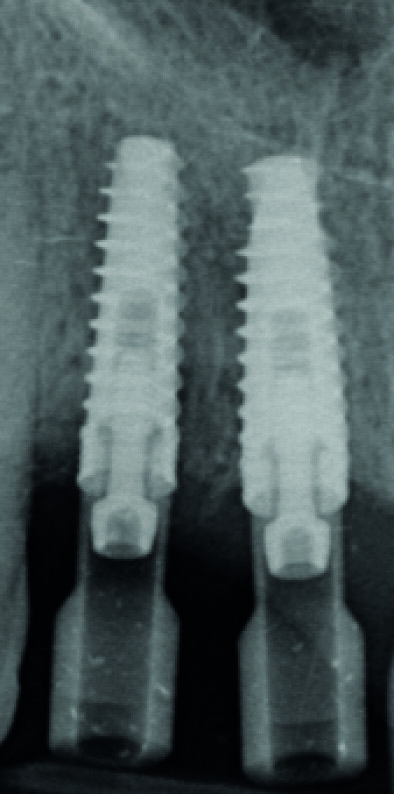

Fig. 7 : Radiographie « long-cône » postopératoire. Notez l’image résiduelle de l’alvéole au niveau de l’implant en 12.

Fig. 8 : Radiographie « long-cône » de contrôle à deux mois.

Fig. 9 : Radiographie « long-cône » de contrôle à trois mois. Notez la progression de la cicatrisation osseuse au niveau de l’implant en 12.

Fig. 18 : Radiographie de contrôle. Notez la parfaite adaptation des différents éléments prothétiques.

Notez aussi la très bonne cicatrisation osseuse péri-implantaire surtout en 12 (comparaison possible avec la figure 7).

La patiente est revue à huit jours. Les suites opératoires se sont bien passées et la prise d’antalgique très limitée. Les sutures sont retirées. Puis la patiente est revue en contrôle à deux mois (Fig. 8), trois mois (Fig. 9) et quatre mois. Les radiographies de contrôles montrent un gain osseux au niveau de l’implant en 12 et une parfaite intégration des deux implants. Les cicatrisations clinique et osseuse sont très bonnes et il est décidé de passer à la prothèse définitive. Les couronnes et piliers provisoires sont retirés et les tissus mous vérifiés (Fig. 10).